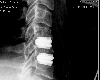

The end result - artifical discs. The old discs have been removed, the offending bits of bone removed, and the new joints inserted.